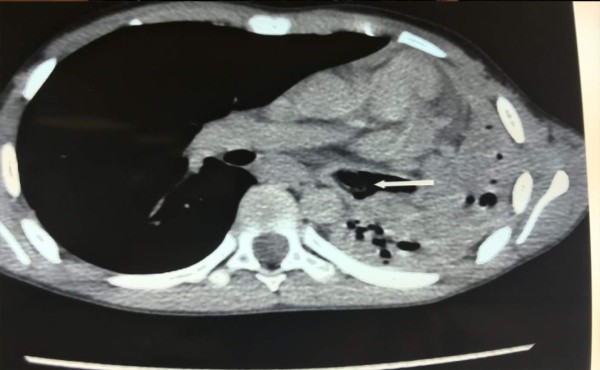

Foto: La Prensa

Radiografía muestra el punto exacto donde se encontraba el tapón de bolígrafo.